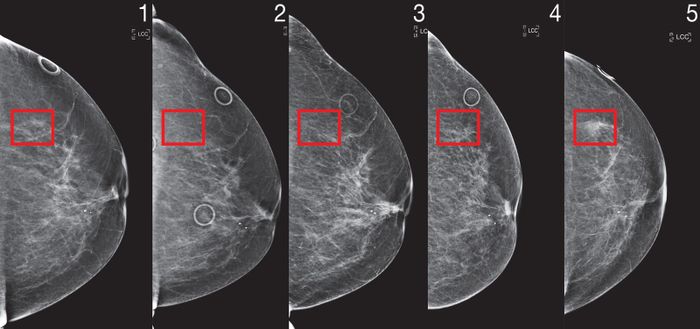

Thuật toán phân tích các hình ảnh siêu âm trước đó, và dường như hoạt động ngay cả khi bác sĩ không nhận thấy dấu hiệu cảnh báo trong những lần quét trước đó. “Những công cụ Trí Tuệ Nhân Tạo đang làm là họ đang trích xuất thông tin mà mắt và não tôi không thể,” cô nói.

Để tạo ra Mirai, Yala đã phải vượt qua những vấn đề mà đã làm khó khăn cho những nỗ lực khác trong việc sử dụng Trí Tuệ Nhân Tạo trong chẩn đoán xạ trị. Anh ta đã sử dụng phương pháp học máy thù địch, trong đó một thuật toán cố gắng lừa dối một thuật toán khác, để giải quyết sự khác biệt giữa các máy xạ trị, điều này có thể làm cho bệnh nhân có cùng nguy cơ mắc bệnh ung thư vú nhận điểm khác nhau. Mô hình cũng được thiết kế để tổng hợp dữ liệu từ nhiều năm, làm cho nó chính xác hơn so với những nỗ lực trước đó chỉ bao gồm ít dữ liệu.

Thuật toán MIT phân tích bốn góc nhìn tiêu chuẩn trong một hình ảnh siêu âm, từ đó suy luận thông tin về bệnh nhân thường không được thu thập, chẳng hạn như lịch sử phẫu thuật hoặc yếu tố hormone như mãn kinh. Điều này có thể hữu ích nếu dữ liệu đó chưa được thu thập bởi bác sĩ trước đó. Chi tiết về công việc được trình bày trong một bài báo được xuất bản ngày hôm nay trong tạp chí Y học Chuyển giao Khoa học.